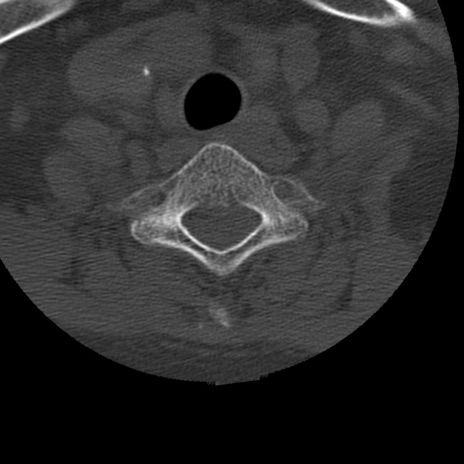

症例50 頚椎CT(横断像)

頚椎CT